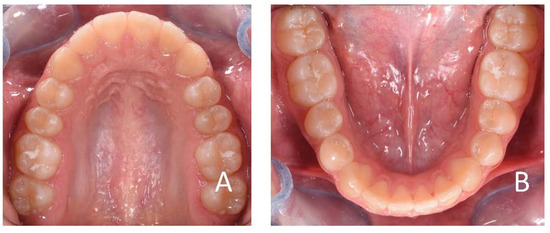

3.1. Clinical Case #1

3.2. Clinical Case #2